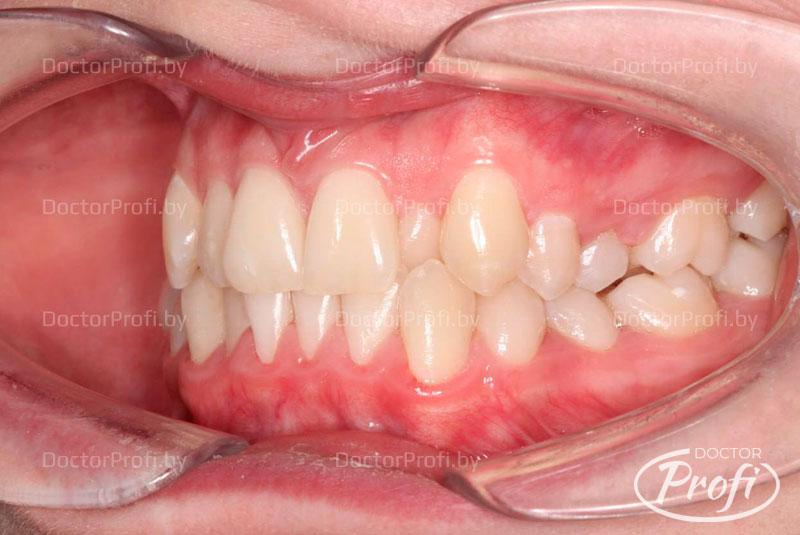

На основании полученных данных был установлен диагноз: двусторонний буккально-перекрестный прикус со смещением нижней челюсти вправо, дистальное соотношение зубов справа и тенденция к мезиальному прикусу слева; сужение и укорочение зубных дуг; скученное положение резцов на верхней и нижней челюсти с полным дефицитом места для зуба 22, а также истирание твердых тканей зуба 22 в пределах дентина; множественные ротации зубов и смещение центральной линии верхней челюсти влево на 3 мм.

Лечение проводила врач-ортодонт Дегтерева Илона Валерьевна с использованием самолигирующей брекет-системы Damon Q2 на обеих челюстях с избирательной пришлифовкой эмали на контактных поверхностях зубов во фронтальном отделе.

После снятия брекет-системы были установлены ретейнеры, а эстетическая реставрация зуба 22 была выполнена стоматологом-терапевтом высшей категории медицинского центра «Доктор Профи» Заблотской Екатериной Николаевной.

В результате проведенного лечения удалось достичь впечатляющих эстетических и функциональных результатов, что позволило пациентке обрести уверенность в своей улыбке